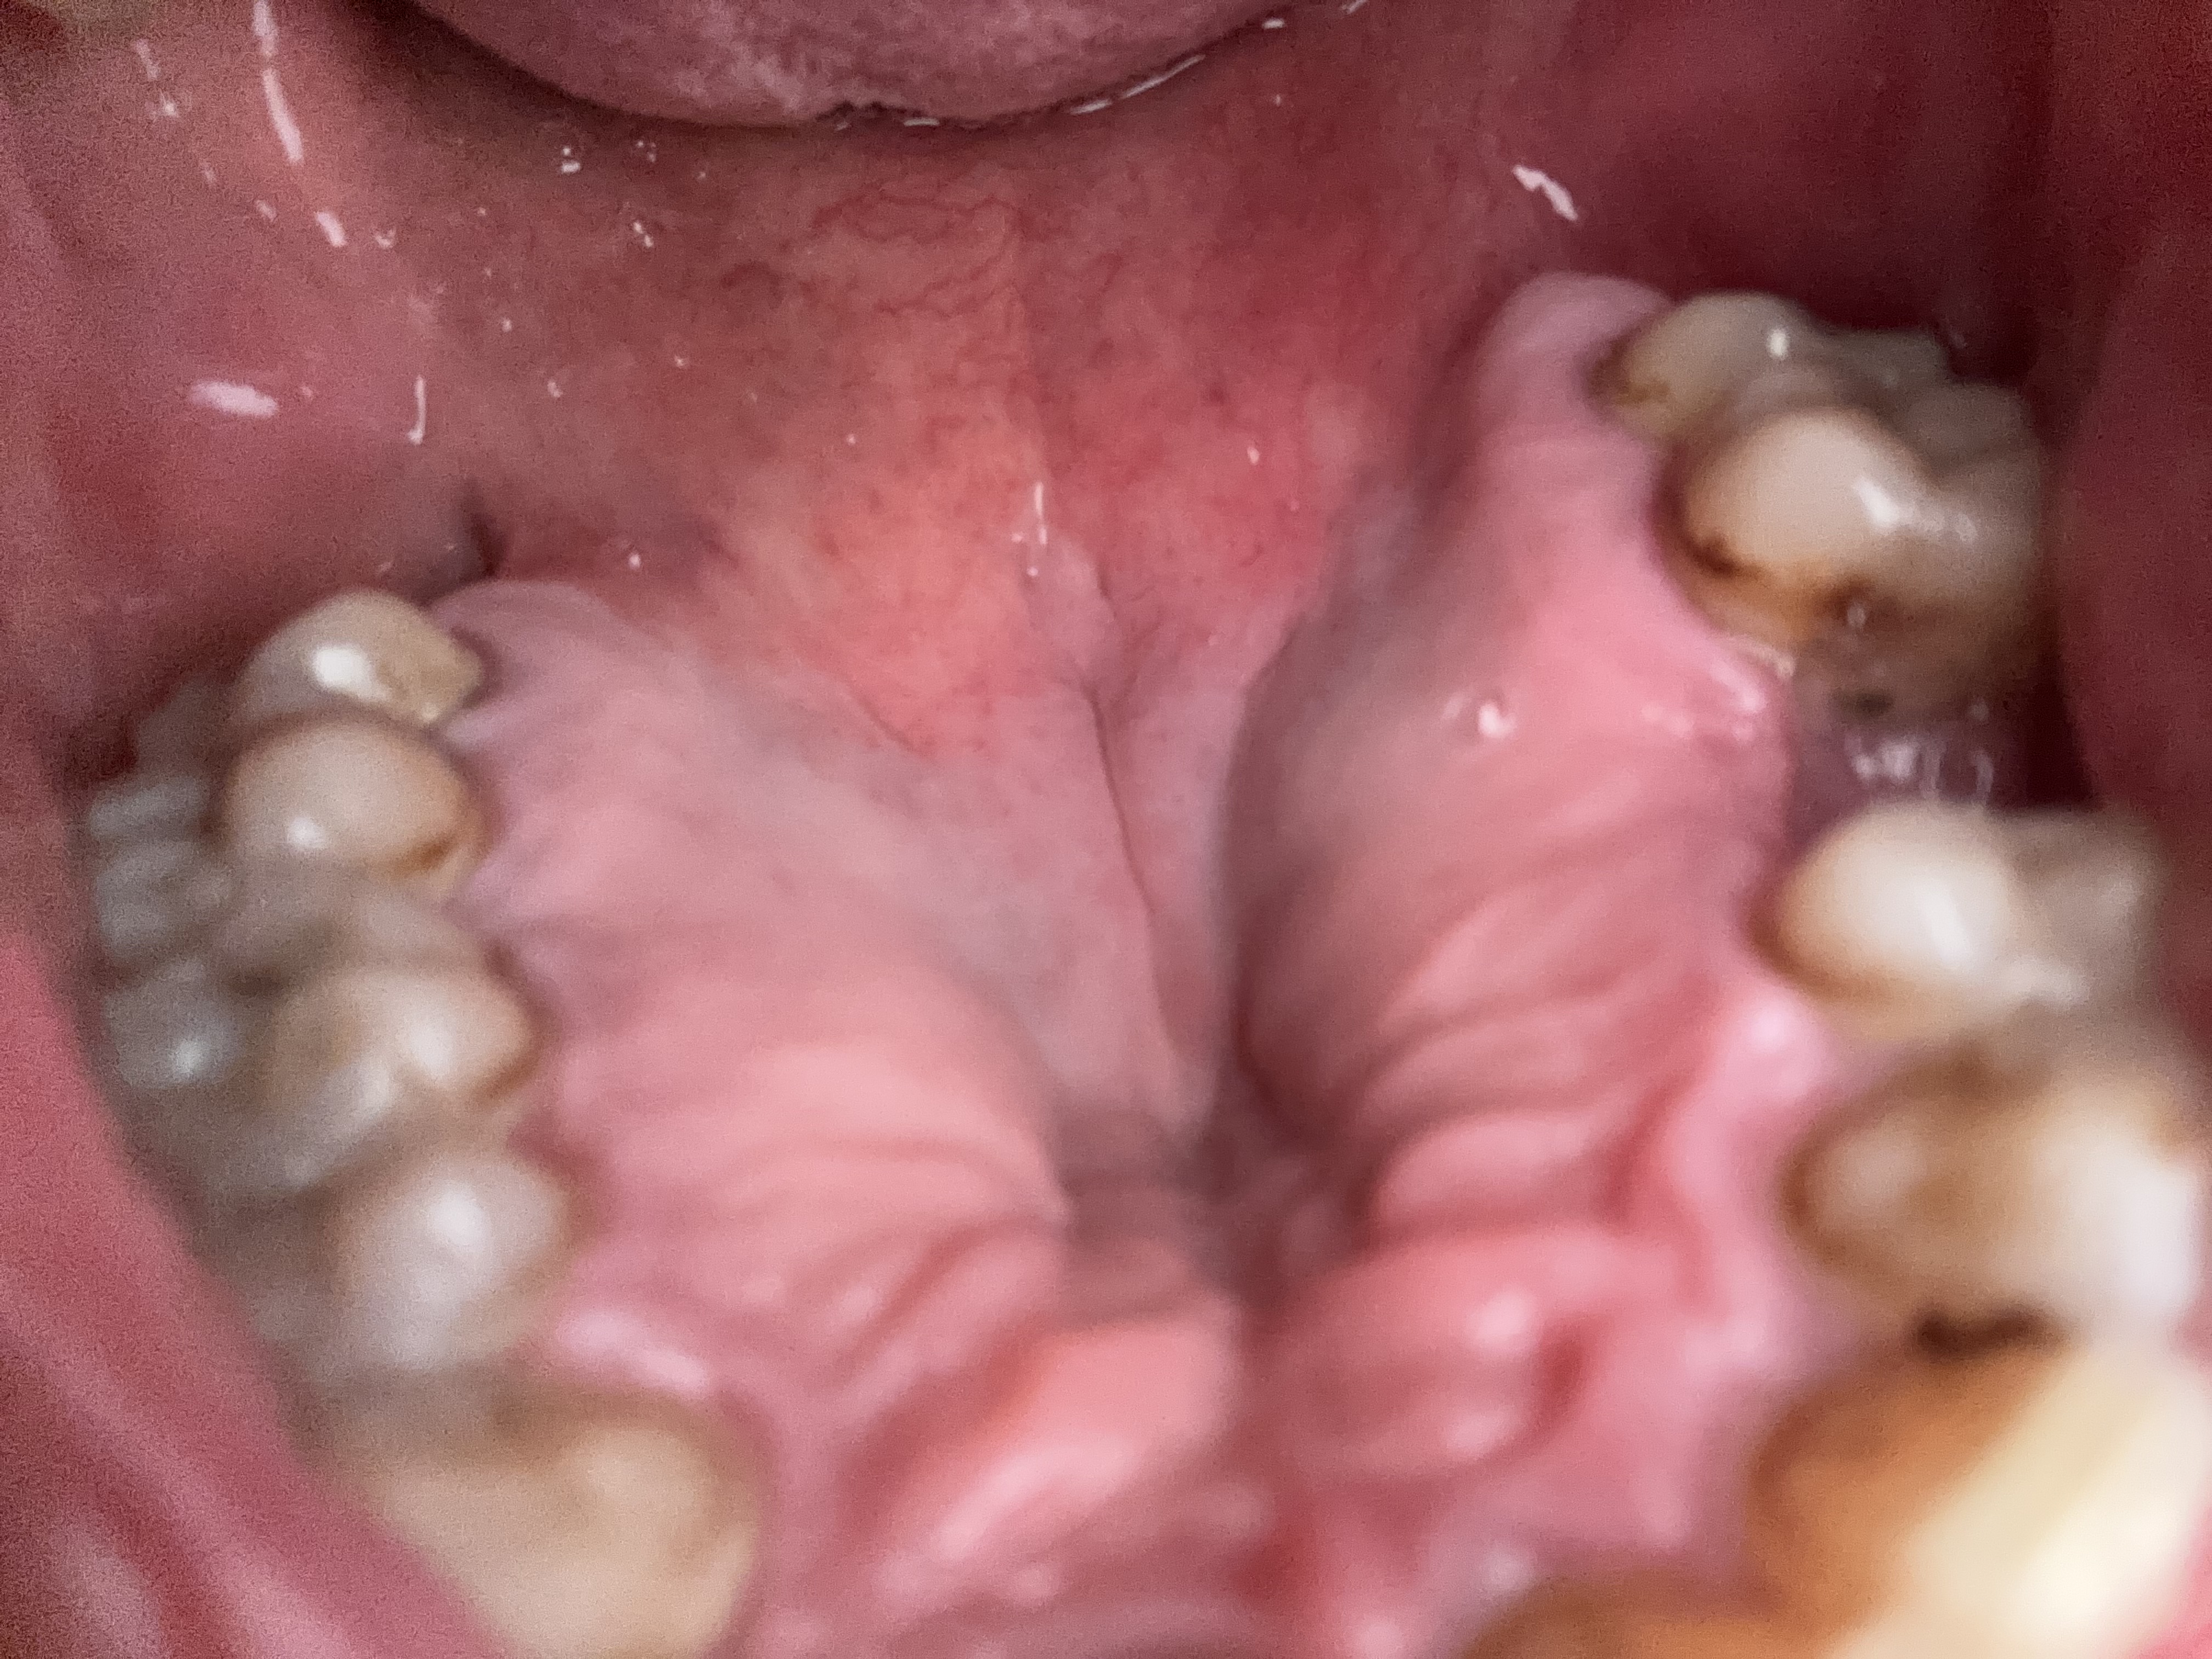

Will I need retainers after Wisdom tooth extraction?

I have never had braces or any other device before. My wisdom teeth (below) have been coming in for a bit but the left one is at an angle. This causes me pain and pressure towards the front of my jaw as my teeth and being forced together and crowding. Will I need retainers after I remove the wisdom tooth?